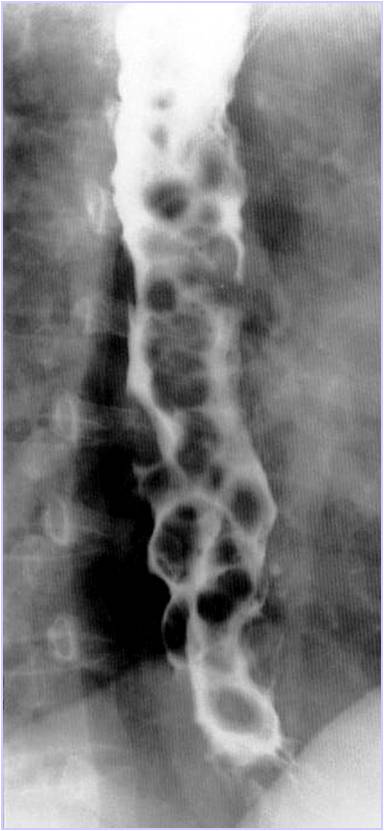

Create and publish online surveys in minutes, and view results graphically and. Esophageal varices 2 - radRounds Radiology Network

Esophageal varices 2 - radRounds Radiology Network from storage.ning.com

750 million+ members | manage your professional identity. Esophageal varices 2 - radRounds Radiology Network